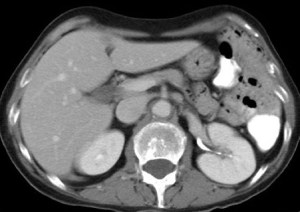

CASO 2: Paciente de 68 años con dolor en flanco izquierdo, fiebre y malestar general. A la exploración existe enrojecimiento de la piel con sensación de masa palpable y puño percusión muy positiva.

El paciente es alégrico al Iodo. Se realiza TC sin contraste para ampliar estudio.

Todos estos hallazgos están en relación con una Pielonefritis Xantunogranulomatosa que afecta al riñón derecho junto con una colección que ha fistulizado a región lumbar.

- Pielonefritis Xantunogranulomatosa.

- Es una forma infrecuente de pielonefritis crónica, de origen obstructivo, caracterizada por la formación de un absceso granulomatoso que puede extenderse al EPR-, severa destrucción renal y un cuadro clínico de fiebre, malestar general, dolor en el flanco y masa renal, a veces palpable.

- En placa simple podía verse un masa que renal con o sin borramiento de la línea del psoas. En ecografía, cálculos y aumento del tamaño renal en la forma difusa con múltiples áreas anecoicas correspondientes a las colecciones purulentas.

- Los hallazgos en TC pueden ser:

- Uni o bilateralidad de la lesión.

- Afección difusa o localizado.

- Litiasis de tipo coraliforme, calcificaciones intraparenquimatosas.

- Aumento difuso del tamaño renal.

- Áreas hipodensas o hipoecogénicas dentro de la lesión renal debidas a cálices dilatados, abscesos o áreas de necrosis parenquimatosa.

- Pobre o nula eliminación del medio de contraste en el riñón afectado.

- Compromiso inflamatorio que excede los límites del riñón y genera colecciones periféricas o extensión hacia vísceras vecinas.